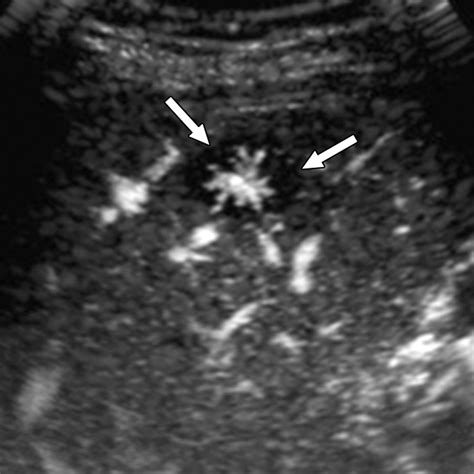

• Ultrasound: This non-invasive test uses sound waves to create images of the liver. It can detect the presence of a nodule but may not provide enough detail to confirm FNH.

• Liver Biopsy: In some cases, a liver biopsy may be performed to confirm the diagnosis. This involves taking a small sample of liver tissue for examination under a microscope.